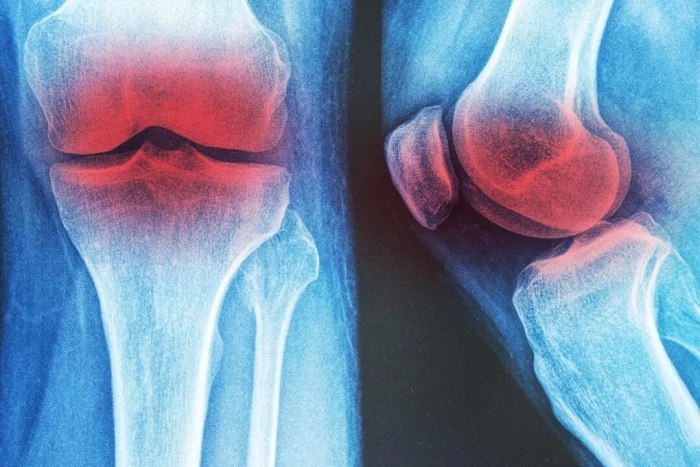

Три немедикаментозных метода лечения остеоартрита коленного сустава

Учёные обнаружили, что при остеоартрите коленного сустава наилучшим выбором были наколенники, гидротерапия и общие физические упражнения.